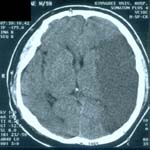

<µÎ°³°ñÀý>

<¼±»ó°ñÀý>

<ÇÔ¸ô°ñÀý>

µÎ°³°ñÀýÀÇ

³úCT ¼Ò°ß

<±Þ¼º°æ¸·¿ÜÃâÇ÷>

<¸¸¼º°æ¸·ÇÏÃâÇ÷>

ÁÂ)

ÁÂÃø ÃøµÎºÎ¿¡ ·»Áî¸ð¾çÀÇ °æ¸·¿Ü ÃâÇ÷ÀÇ

CT¼Ò°ß

¿ì) °æµµÀÇ ¿Ü»ó¿¡µµ

¹ß»ýÇÏ°Ô µÇ´Â ¸¸¼º°æ¸·ÇÏÃâÇ÷ÀÇ ³úMRI¼Ò°ß